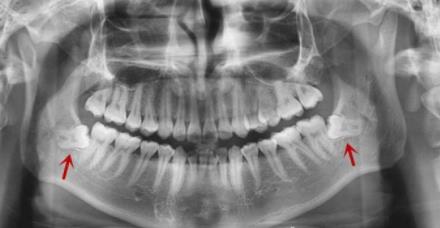

比如檢查有無智齒,查看智齒生長位置及方向,一般拍全景片(可以看到全口牙齒情況的那種牙片)就可以看到智齒的情況了。但是呢,如果全景片智齒的位置不清楚,而且接近牙神經,需要進一步確認情況的話,可能還需要拍CT片。

智齒的小牙片